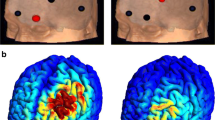

In the operative phase (phase 3), participants had routine pre-operative evaluations and MRI. Using MRI neuro-navigation, two Lamitrode 44 electrodes (Abbot, Neurodivision, Plano, Texas) were placed on the dACC under general anaesthesia (Fig. 1), followed by overnight observation in a neurosurgical high dependency unit.

At a whole-brain level, after correcting for multiple comparisons, in responders, there was a significant decrease in current density at the rdACC for beta 1 band (t(5) = 1.6, p = 0.026) (Fig. 5a). No significant effects were observed for the delta, theta, alpha 1, alpha 2, beta 2, beta 3 and gamma bands in the rdACC. Also, there were no significant differences between responders at pre- and post-stimulation and healthy controls for all bands.

As for ROI analysis for beta 1 band in the rdACC, there was a significant decrease (mean change ± SD = 1.22 ± 0.61) (t(5) = 5.0, p = 0.004) in log-transformed current density pre-stimulation (mean ± SD = 2.8 ± 0.5) and post-stimulation (mean ± SD = 1.6 ± 0.4) (Fig. 5b).